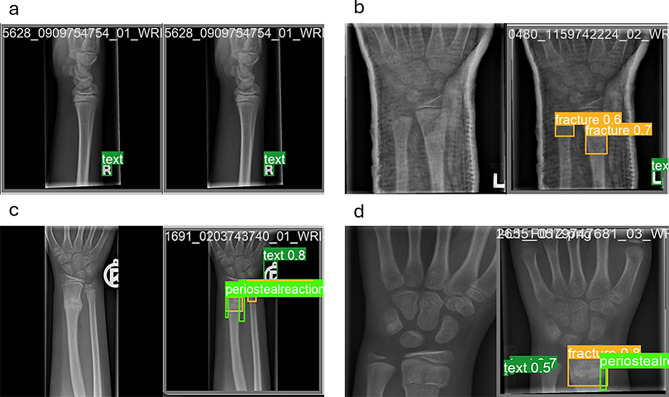

Background: In emergency departments, residents and physicians interpret X-rays to identify fractures, with distal radius fractures being the most common in children. Skilled radiologists typically ensure accurate readings in well-resourced hospitals, but rural areas often lack this expertise, leading to lower diagnostic accuracy and potential delays in treatment. Machine learning systems offer promising solutions by detecting subtle features that non-experts might miss. Recent advancements, including YOLOv8 and its attention-mechanism models, YOLOv8-AM, have shown potential in automated fracture detection. This study aims to refine the YOLOv8-AM model to improve the detection of distal radius fractures in pediatric patients by integrating targeted improvements and new attention mechanisms.

Methods: We enhanced the YOLOv8-AM model to improve pediatric wrist fracture detection, maintaining the YOLOv8 backbone while integrating attention mechanisms such as the Convolutional Block Attention Module (CBAM) and the Global Context (GC) block. We optimized the model through hyperparameter tuning, implementing data cleaning, augmentation, and normalization techniques using the GRAZPEDWRI-DX dataset. This process addressed class imbalances and significantly improved model performance, with mean Average Precision (mAP) increasing from 63.6 to 66.32%.

Results and discussion: The iYOLOv8 models demonstrated substantial improvements in performance metrics. The iYOLOv8 + GC model achieved the highest precision at 97.2%, with an F1-score of 67% and an mAP50 of 69.5%, requiring only 3.62 h of training time. In comparison, the iYOLOv8 + ECA model reached 96.7% precision, significantly reducing training time from 8.54 to 2.16 h. The various iYOLOv8-AM models achieved an average accuracy of 96.42% in fracture detection, although performance for detecting bone anomalies and soft tissues was lower due to dataset constraints. The improvements highlight the model's effectiveness in pathological detection of the pediatric distal radius, suggesting that integrating these AI models into clinical practice could significantly enhance diagnostic efficiency.